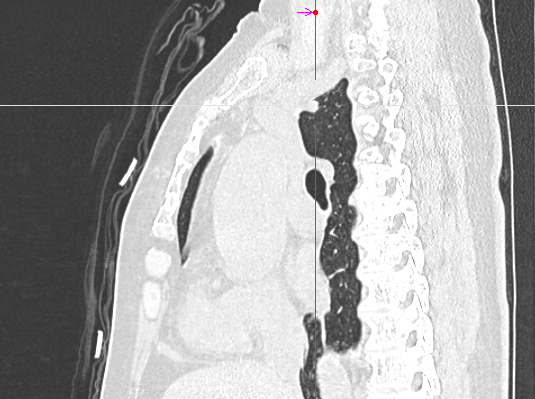

数月前,66岁的龚女士在肺癌术后随访复查中,胸部CT报告显示其右上肺新发实性结节一枚,并由刚开始发现时的5mm逐步增大至10mm。更棘手的是,这个结节位于右肺上叶尖段的纵隔胸膜下,位置极其“刁钻”。面对这份报告,患者龚女士陷入了深深的焦虑。因为其7年前因右中肺肿瘤行右中肺癌根治术,对于新发的实性结节为何种性质,是新发肺恶性肿瘤或是良性病变,亦或是原肺癌复发转移,目前均不能明确。辗转多家医院,得到的建议多为“定期观察,等待变化”或考虑创伤较大的传统穿刺活检,但结节位置非常深,单纯CT引导下定位穿刺很难精准到达,且需穿行的肺组织较多,创伤较大。

胸外科马海涛主任团队对龚女士的病情进行了深入细致的评估:结节虽小,但形态学特征具有风险,且结节逐步增大,结合既往肺癌病史,考虑肿瘤复发可能,“定期观察”方案会让患者持续承受心理煎熬。然而,传统的CT引导下经皮肺穿刺定位,对于如此深部、微小的结节,极易导致气胸、出血等并发症,风险极高。

马主任解释系统原理:“这套系统就像为我们医生的操作装上了‘肺部GPS’。它通过术前将患者的CT影像数据导入系统,构建出独一无二的肺部三维‘地图’。术中,在磁场的引导下,我们操控一根细如发丝的导航探头,经由患者的口腔、气管这一自然通道,毫无创伤地直达常规支气管镜无法到达的肺外周深处,精准地停靠在目标结节旁边。磁导航支气管镜的优势是决定性的。它实现了‘经自然腔道、无创抵达’,彻底避免了经皮穿刺可能引起的高达20%-30%的气胸风险,为定位深部结节提供了安全、精准的解决方案。”